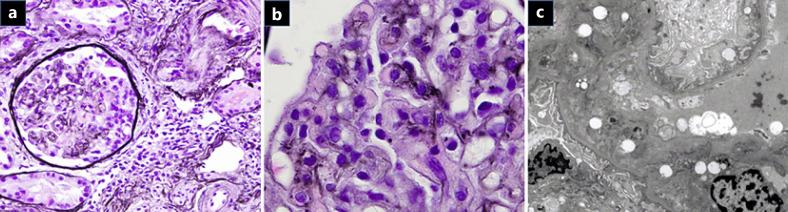

A 69-year-old man with refractory lung adenocarcinoma was treated with gemcitabine and vinorelbine. Dyspnea and hypertension developed after the 17th cycle of chemotherapy. Laboratory findings revealed intravascular hemolysis and renal dysfunction. Thrombotic microangiopathy (TMA) was confirmed by renal biopsy. Antihypertensive and steroid therapies were ineffective. After plasmapheresis, intravascular hemolysis and renal dysfunction gradually improved. However, the disease progressed, and he died 6 months after TMA diagnosis. Autopsy revealed similar pathological findings to those of the renal biopsy. It is important to discontinue gemcitabine at the onset of TMA and consider TMA when using gemcitabine for long periods.

一名69岁的难治性肺腺癌男性患者接受了吉西他滨和长春瑞滨治疗。在第17周期化疗后出现呼吸困难和高血压。实验室检查发现血管内溶血和肾功能不全。肾活检确诊为血栓性微血管病(TMA)。抗高血压和类固醇治疗无效。血浆置换后,血管内溶血和肾功能不全逐渐改善。然而,疾病进展,他在TMA诊断后6个月死亡。尸检显示与肾活检相似的病理结果。在TMA发作时停用吉西他滨并在长期使用吉西他滨时考虑TMA很重要。